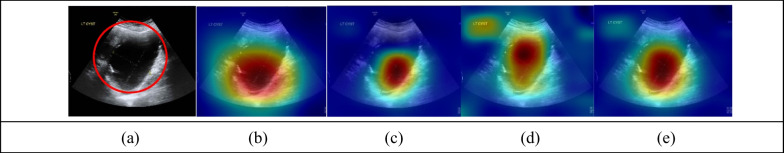

After obtaining the model interpretation results, we used Grad-CAM to generate heat maps and invited experts to discuss with us the acceptability of the models’ explanations. Figure 6 presents an example of images that were compared and discussed. The red circle in Fig. 6a is the lesion site identified by experts. Figure 6b–d represent the areas that drew the most attention from ResNet-18, ResNet-50, and Xception. Although both model and expert interpretations classified the tumor as benign, ResNet-18’s area of attention (see Fig. 6b) was the closest to that of expert interpretations. By contrast, Xception’s area of attention (Fig. 6d) was partially out of focus, and it was partially focused on the background and text; therefore, Xception’s interpretation lacked persuasiveness. We decided to combine the perspectives of all three models by superimposing and averaging their heat maps, thereby creating Fig. 6e. As indicated by Fig. 6e, the degree of attention paid to the background and ovarian tumor decreased and increased, respectively. In Fig. 6e, the area of attention was closest to that of expert interpretations. The heat map produced by superimposing and averaging the three model heat maps aligned more closely with the discussion results of the three experts.

Fig. 6.

Comparison of expert interpretations with heat maps of each model. a Red circle is lesion site identified by experts. b–d Areas that drew the most attention from ResNet-18, ResNet-50, and Xception. e Heap map generated by superimposing and averaging heat maps of three models; its area of attention is most closely aligned with that of expert interpretations